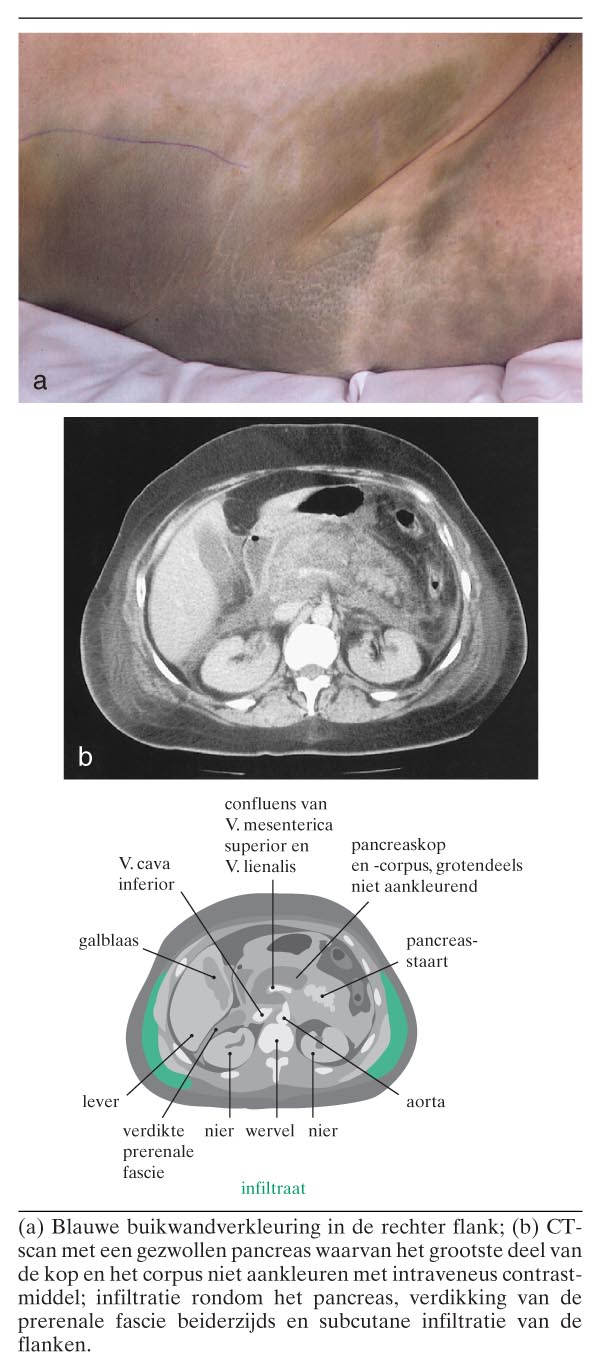

Een 59-jarige vrouw werd opgenomen op de afdeling Intensive Care ter behandeling van een diepe shock en multipel orgaanfalen ten gevolge van een acute pancreatitis met onbekende oorzaak. Op de tweede dag werd beiderzijds in de flanken een blauwe verkleuring zichtbaar: het teken van Grey Turner (figuur a). Het CT-beeld staat in de figuur (b). Na een aanvankelijk herstel ontstond op de 13e dag opnieuw een diepe septische shock. Bij spoedlaparotomie bleken grote delen van de dunne en de dikke darm necrotisch, met perforatie van het sigmoïd. Het pancreas was volledig genecrotiseerd. Patiënte overleed tijdens de…